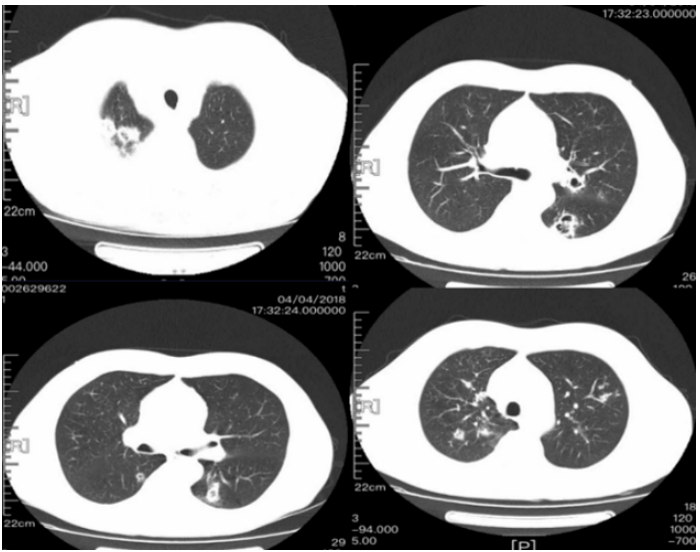

病毒性肺炎是由各种呼吸道病毒感染引发的肺实质炎症,容易并发呼吸衰竭,常见于幼儿(<5岁)和年龄>50岁的成人。WHO数据显示:社区获得性肺炎(CAP)中病毒性肺炎占20%~40%,在ICU中比例稍高,为30%~40%。常见病毒性肺炎的病原体包括流感病毒、鼻病毒、呼吸道合胞病毒、腺病毒、人偏肺病毒、巨细胞病毒、冠状病毒等。病毒性肺炎的常见影像学特征如下:图1所示为COVID-19的高分辨率CT(HRCT):在急性期,图1A为双肺弥漫性磨玻璃影(GGO),图1B为小叶周围型,图1C和D表现为亚急性间质性肺炎,GGO减少,主要为胸膜下局灶性实变和小叶间/小叶内间质增厚。图2A-C显示了一例与COVID-19间质改变相似的甲型流感病例:GGO主要分布在胸膜下和双侧,呈小叶周围性分布。图2D为同一患者的仰卧位胸片,可见弥漫性肺间质受累。图3A-D为一例H1N1相关肺炎并发急性呼吸窘迫综合征(ARDS)的影像,可见弥漫性、双侧GGO以及牵拉性支气管扩张。图4A显示了一例急性腺病毒肺炎,具有典型的多灶性和大叶GGO,图4B-C显示其导致的长期后遗症——Swyer–James综合征的表现。图5所示为一例疱疹病毒性肺炎,可见双侧分布呈斑片状的GGO(主要位于两肺上叶)。一项基于对美国大规模人群分析的前瞻性多中心研究显示,病毒性肺炎的患病率和发病率随年龄而异,其累积发生率约为22%。研究纳入2222例儿童,其中66%(共1472例)报告有病毒感染,在155例(7%)病例中发现病毒和细菌合并感染。事实上,呼吸道病毒、腺病毒和人偏肺病毒在5岁以下儿童中比较常见。在同一研究的2259例成年人患者中,只有853例(38%)患者检测到病原体,530例(23%)患有病毒性肺炎,59例(3%)发现合并感染。

注:CDC和NIH对于新冠背景下免疫低下人群的定义:癌症治疗人群、实体器官移植受者、原发性免疫缺陷、晚期或未经治疗的HIV感染者或长期使用高剂量糖皮质激素(>20 mg /d)和抑制免疫系统的其他药物(CNI,抗代谢物,生物制剂)。重症COVID-19患者纤支镜下发现支气管黏膜斑片状伪膜或溃疡病变提示CAPA可能。侵袭性曲霉病细支气管炎(IATB)是COVID-19患者罹患侵袭性曲霉病(IA)的重要临床表现之一,在IAPA和CAPA患者中的比率分别为55%和10%~20%,后者的发病率较低,可能与临床医师对此类患者进行气管镜操作的意愿低有关。IAPA和CAPA疾病定义的专家共识中均将气管镜发现的气道病变纳入到细支气管炎型IAPA和CAPA患者的诊断中,具体镜下表现包括:斑片状伪膜或溃疡病灶的形成。在一项COVID-19合并曲霉细支气管炎的队列研究中,图8A为COVID-19伴曲霉细支气管炎患者气管镜下见溃疡和黄白色斑片伪膜形成(箭头);图8B为COVID-19伴曲霉细支气管炎患者尸检中见因黏膜侵袭和溃烂所致支气管软管暴露(箭头);图8C为COVID-19伴ARDS患者气道组织标本中菌丝对细支气管黏膜的侵袭。图8 COVID-19伴曲霉细支气管炎患者支气管镜和病理所见图源:Eur Respir J, 2022, ;59(5):2103142.图9为上海瑞金医院RICU收治的一例流感病毒感染继发侵袭性肺曲霉病(IPA)患者, 从影像学中可以看到病变非常严重, 沿支气管分布, 非常密集, 以及多发空洞坏死(图9)。该患者最终死亡。可见混合感染会给患者带来非常大的危害。

图9 流感病毒感染继发IPA患者的影像学